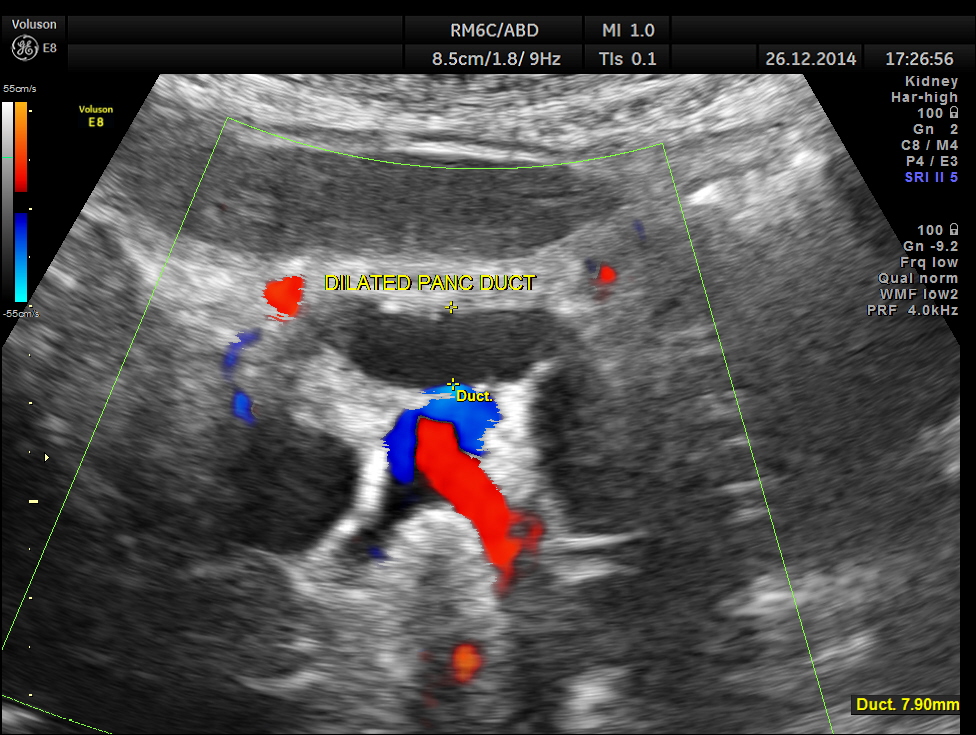

dilated pancreatic duct is seen